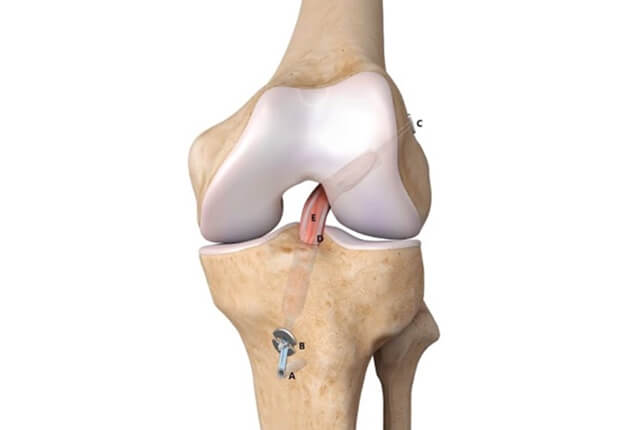

前十字靭帯(ACL)は大腿骨と脛骨をつなぐ靱帯で、後十字靭帯と交差する様に前方に存在します。

半月板は大腿骨と脛骨の間にある線維軟骨です。内側半月板と外側半月板があり、C型の形状をしています。